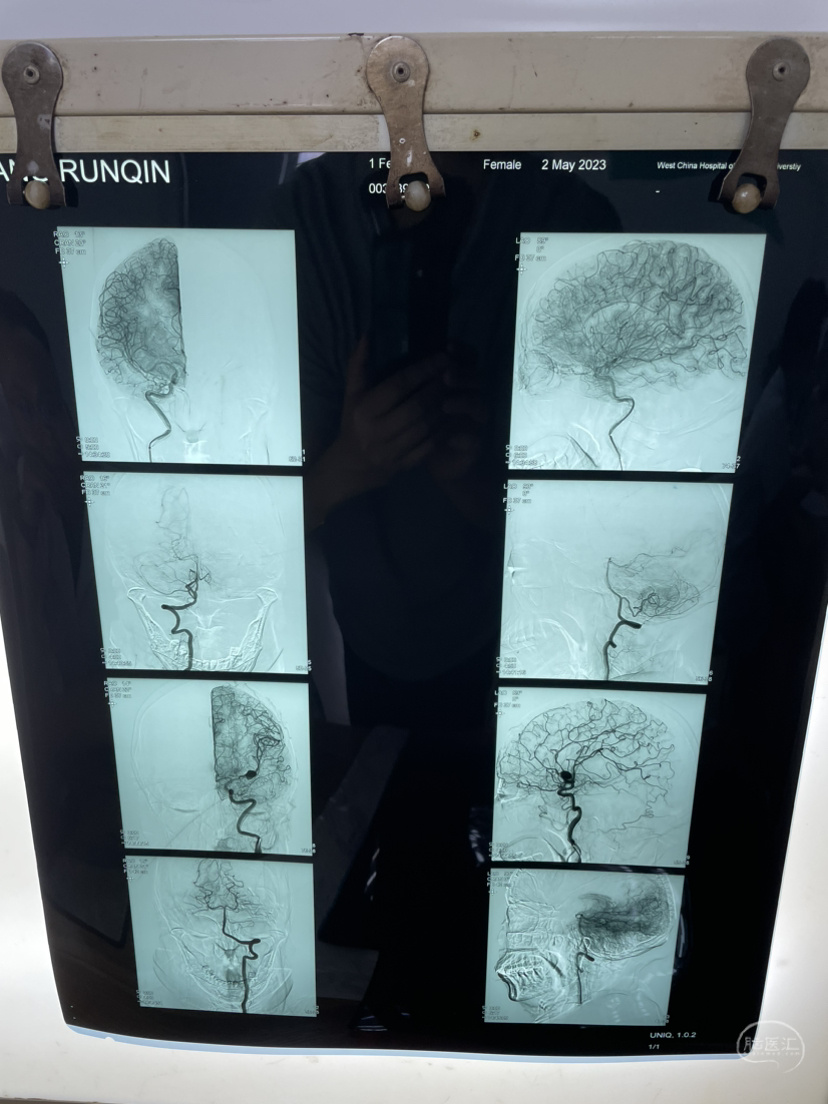

家属选择保守治疗,患者一直清醒!两个月前在华西行介入栓塞术,血肿吸收!

介入栓塞术后两个月来复查!患者清醒轮椅而来,言语稍含糊,右侧下肢肌力可大于三级,上肢一级!